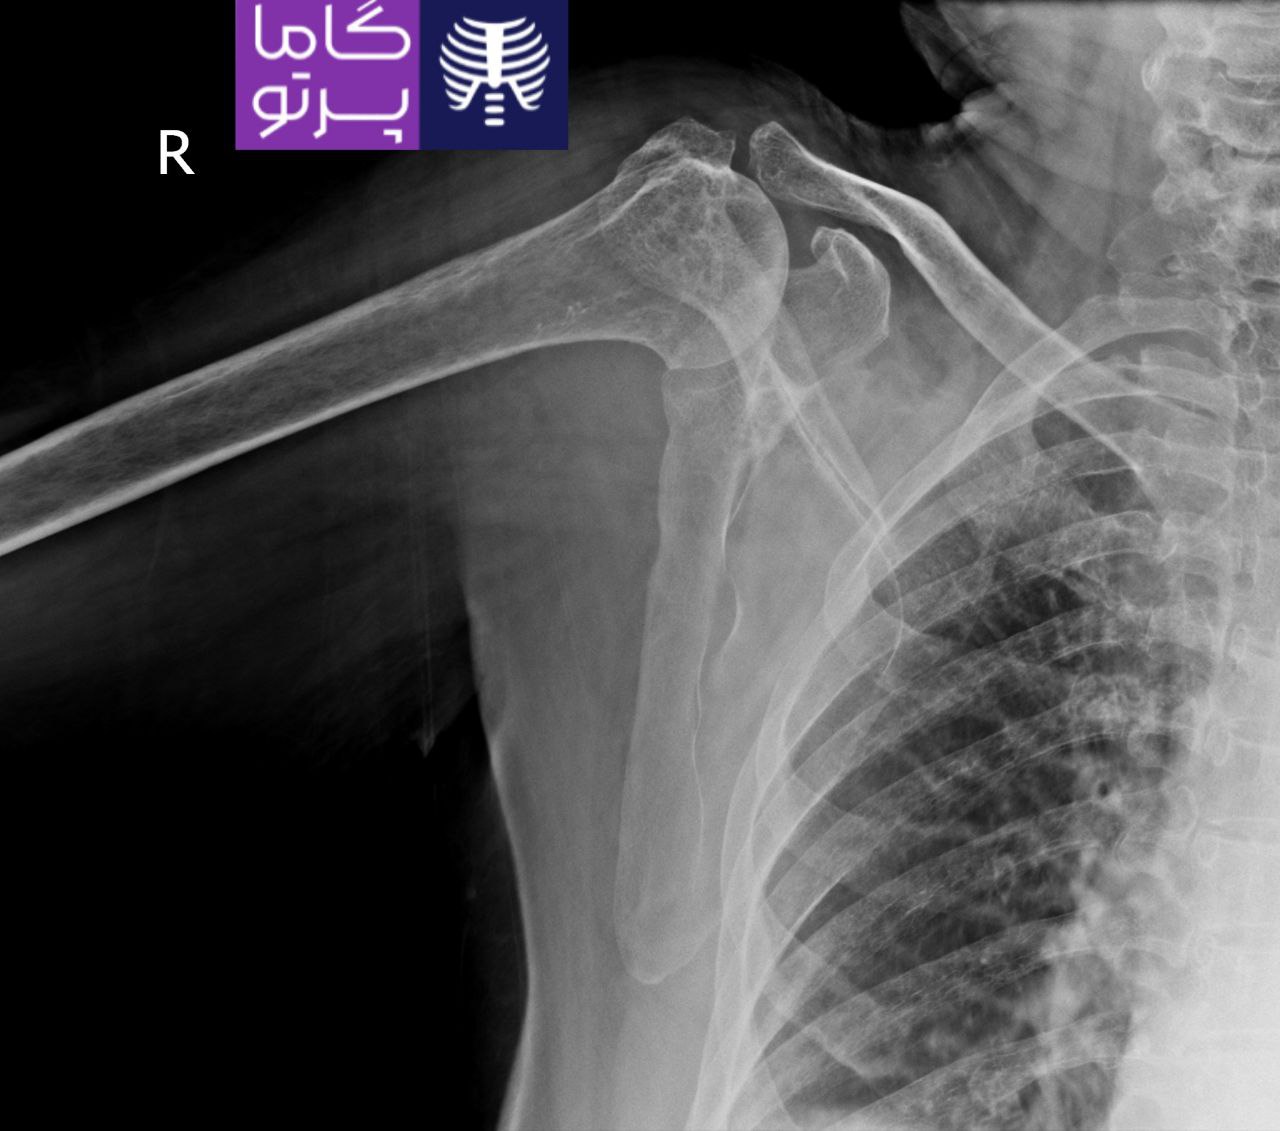

تصاویری از رادیولوژی در منزل توسط گاما پرتو

در این روش تصویر برداری یک صفحه (گیرنده یا دتکتور) در زیر عضو و قسمت مورد نظر قرار داده می شود و اشعه ایکس(دُز از اشعه جهت تشخیص) به همان قسمت که روی صفحه قرار گرفته تابنده می شود و توسط صفحه اطلاعات دریافت می شوند و همین اطلاعات پس از پردازش های لازم در نهایت عکس رادیولوژی به ما ارائه می دهد. کاربردهای رادیولوژی در منزل دقیقاً همان کاربرد رادیولوژی در بیمارستان ها می باشد از جمله بررسی انواع شکستگی ها، دررفتگی مفاصل، آرتروز مفاصل، دیدن پروتز های داخل استخوان از نظر بررسی موقعیت پروتز، آب آوردگی ریه(اِدم وافیوژن) و عفونت ریه، شکستگی دنده ها، انساد و وجود هوا در شکم و… می باشند. رادیولوژی در منزل تمام این خدمات را ارائه می دهد.